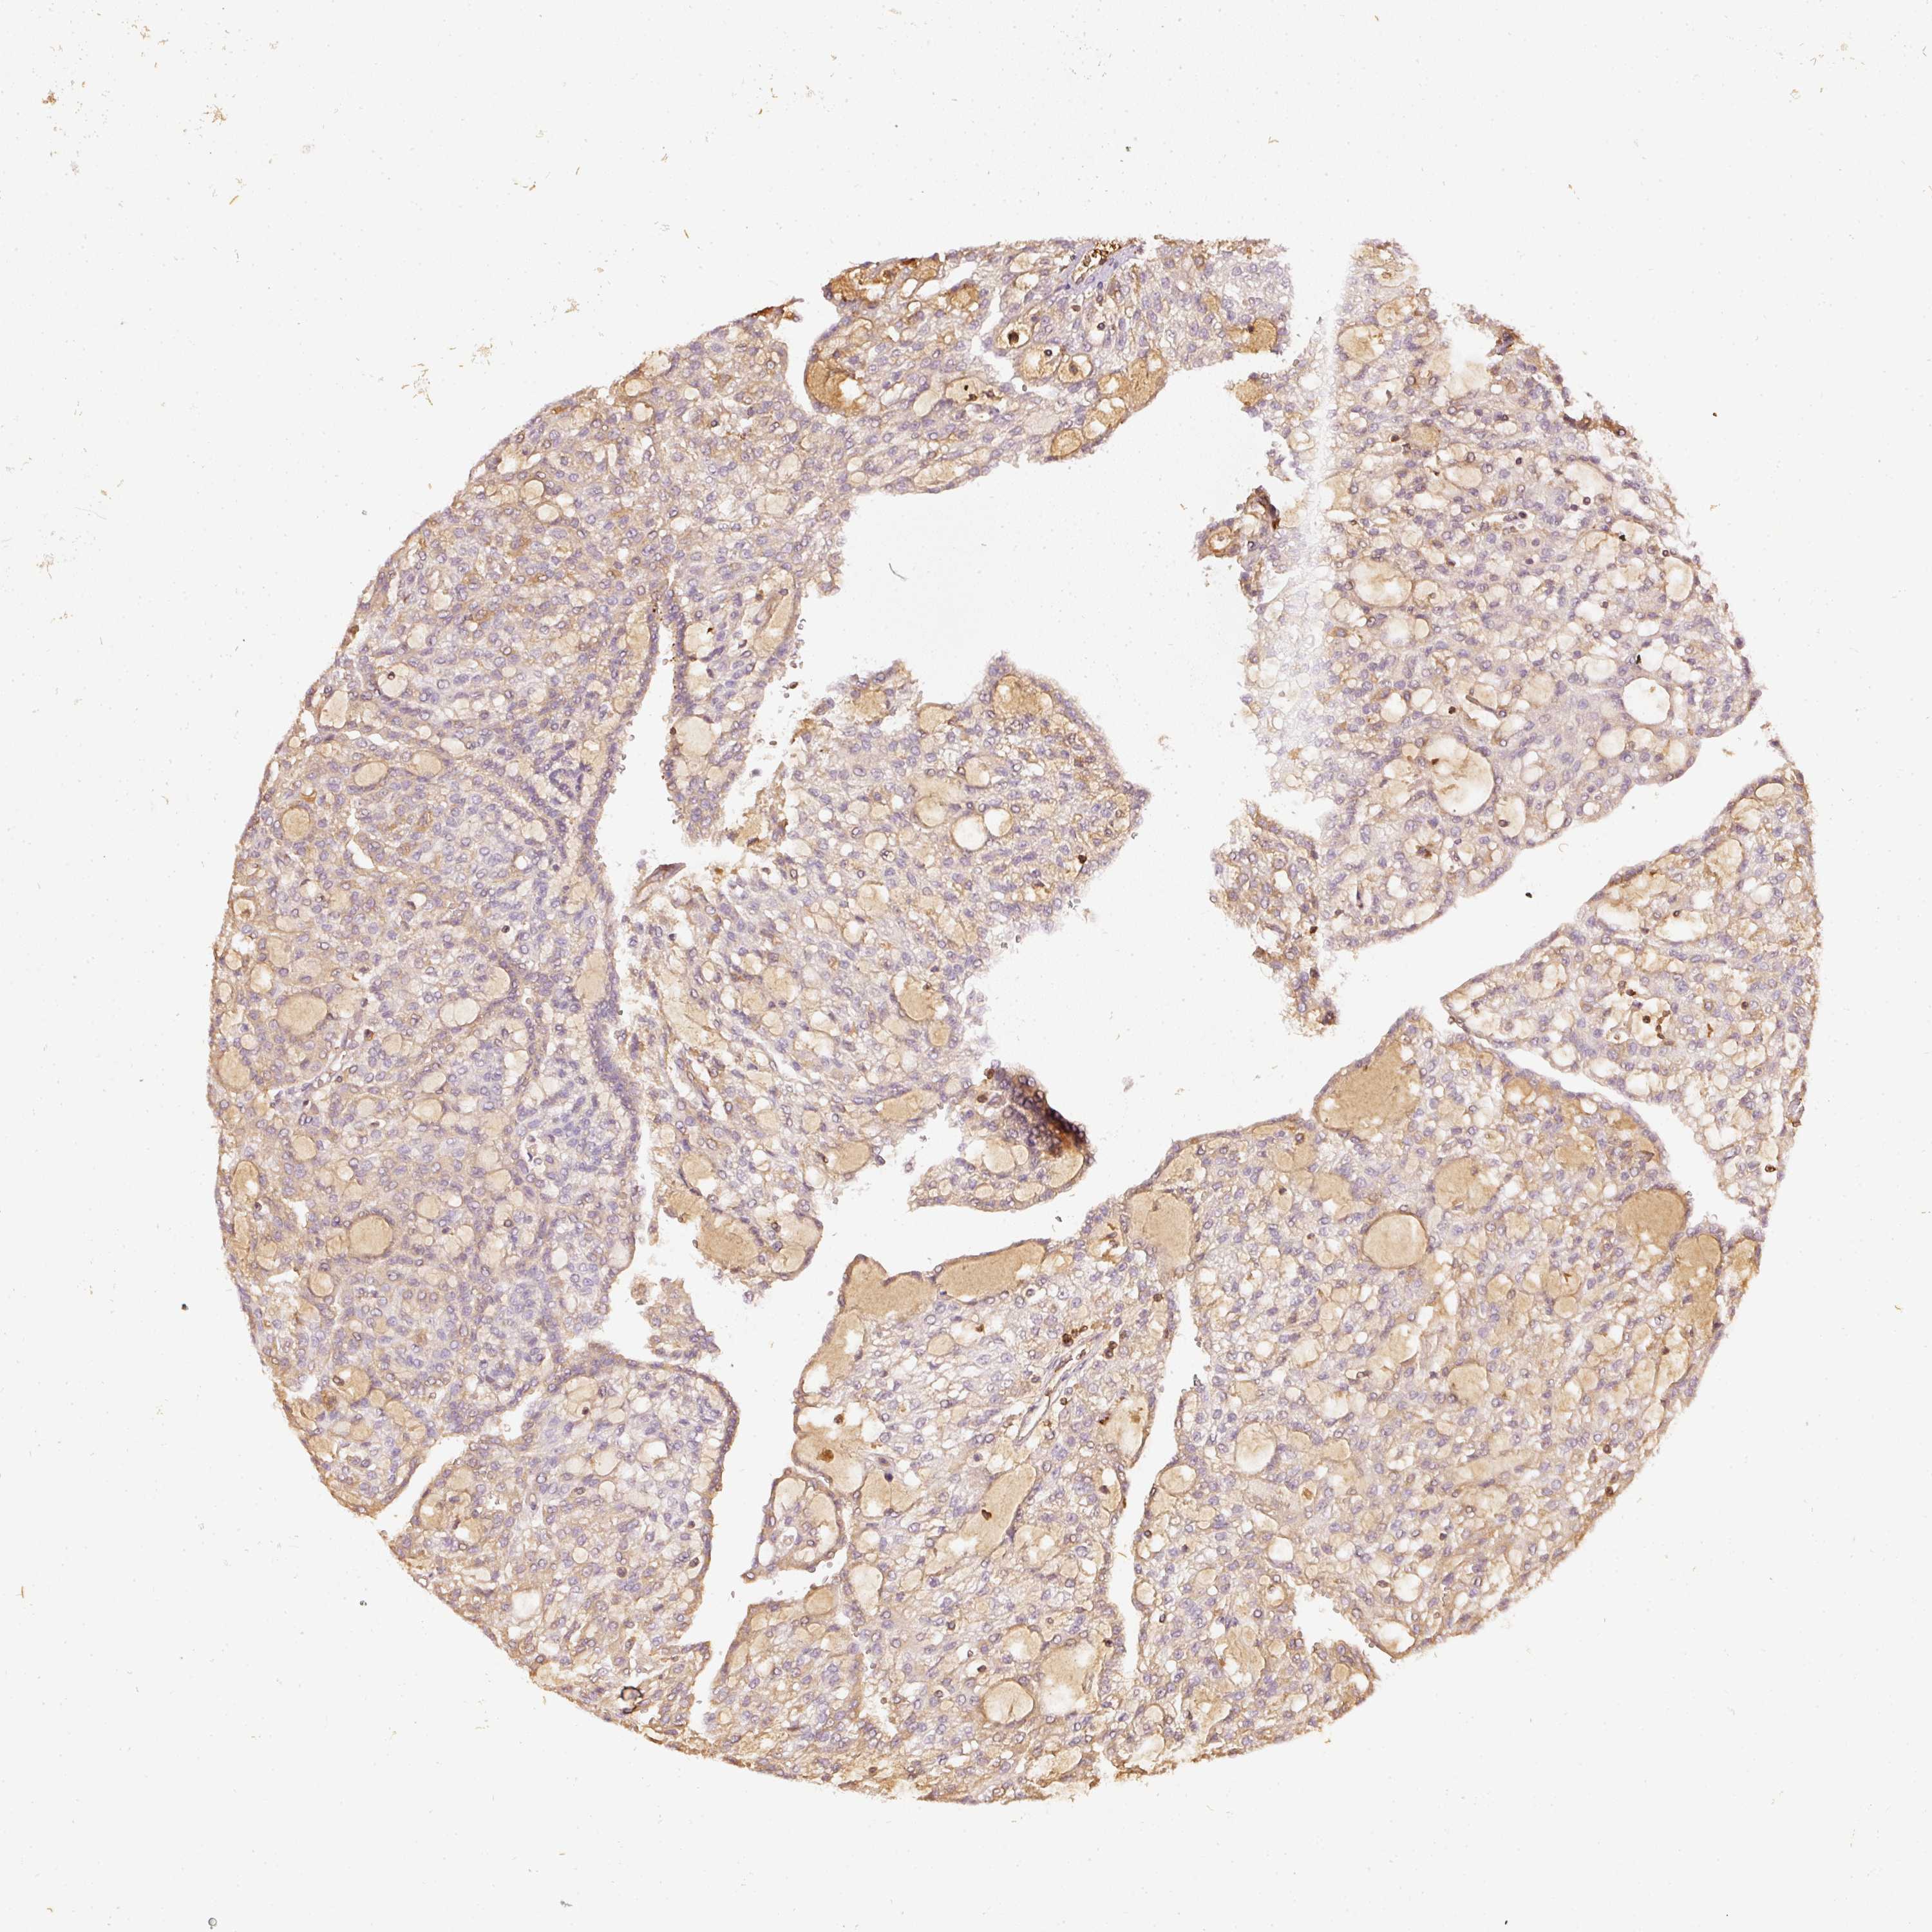

KIDNEY RENAL CLEAR CELL CARCINOMA (VALIDATION) - Interactive survival scatter ploti

The Survival Scatter plot shows the clinical status (i.e. dead or alive) for all individuals in the patient cohort, based on the same data that underlies the corresponding Kaplan-Meier plots. Patients that are alive at last time for follow-up are shown in blue and patients who have died during the study are shown in red.

The x-axis shows the expression levels (FPKM) of the investigated gene in the tumor tissue at the time of diagnosis. The y-axis shows the follow-up time after diagnosis (years). Both axes are complimented with kernel density curves demonstrating the data density over the axes. The top density plot shows the expression levels (FPKM) distribution among dead (red) and alive patients (blue). The right density plot shows the data density of the survived years of dead patients with high and low expression levels respectively, stratified using the cutoff indicated by the vertical dashed line through the Survival Scatter plot. This cutoff is automatically defined based on the FPKM cutoff that minimizes the p-score. The cutoff can be changed by dragging the vertical line or by entering a cutoff value in the square labeled "Current cut-off".

Under the Survival Scatter plot the p-score landscape (black curve; left axis) is shown together with dead median separation (red curve; right axis). Dead median separation is the difference in median mRNA expression between patients who have died with high and low expression, respectively. It is calculated as follows: median FPKM expression of dead patients with high expression - median FPKM expression of dead patients with low expression. This is intended to aid the user in visually exploring custom cutoffs and the associated p-scores and dead median separation.

Individual patient data is displayed and can be filtered by clicking on one or more of the category buttons on the top of the page. Categories describing expression level and patient information include: high, low, alive, dead, female, male and tumor stages. The scale of the x-axis can be toggled between linear and log-scale by clicking on the "x log" button. Mouse-over function shows TCGA ID, patient information and mRNA expression (FPKM) for each patient.

& Survival analysisi

Kaplan-Meier plots summarize results from analysis of correlation between mRNA expression level and patient survival. Patients were divided based on level of expression into one of the two groups "low" (under cut off) or "high" (over cut off). X-axis shows time for survival (years) and y-axis shows the probability of survival, where 1.0 corresponds to 100 percent.

EVL is not prognostic in Kidney Renal Clear Cell Carcinoma (validation)

Best expression cut offi

Based on the FPKM value of each gene, patients were classified into two groups and association between prognosis (survival) and gene expression (FPKM) was examined. The best expression cut-off refers the FPKM value that yields maximal difference with regard to survival between the two groups at the lowest log-rank P-value. Best expression cut-off was selected based on survival analysis .

When clicking on this number, the vertical dashed line indicating cut-off, the interactive survival plot, and the Kaplan-Meier curve will be adjusted to show results based on the best expression cut-off.

: 43.8

TCGA RNA samplesi

RNA-seq data is reported as average FPKM (number Fragments Per Kilobase of exon per Million reads), generated by the The Cancer Genome Atlas (TCGA) .

Normal distribution across the dataset is visualized with box plots, shown as median and 25th and 75th percentiles. Points are displayed as outliers if they are above or below 1.5 times the interquartile range. FPKM values of the individual samples are presented next to the box plot.

Average pTPM 62.3

Number of samples 100